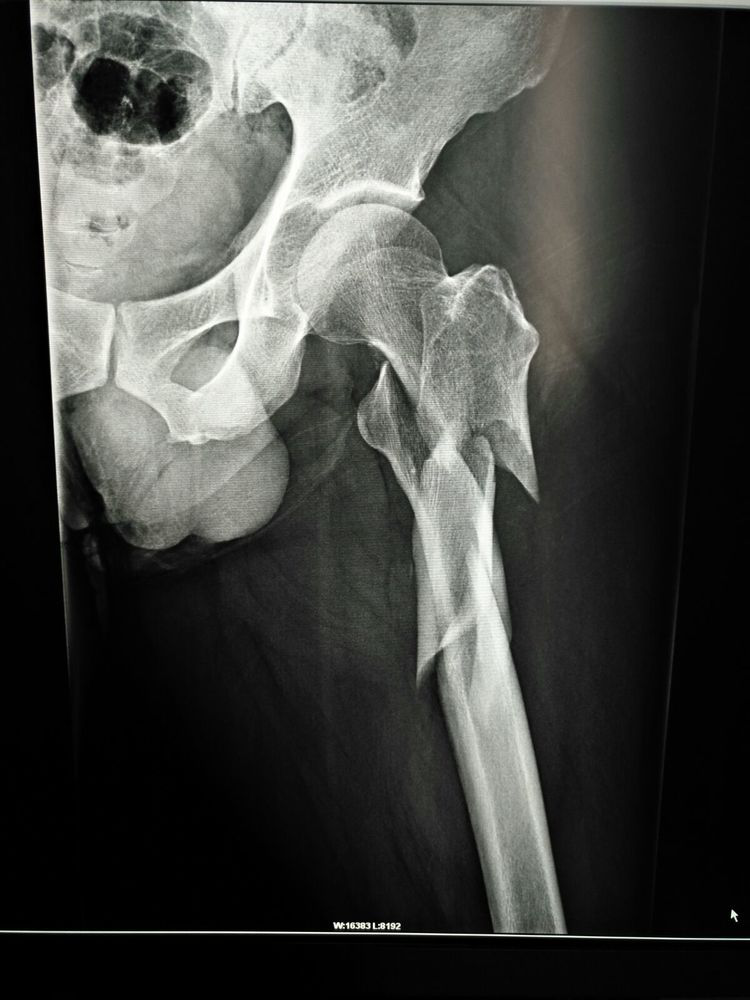

術(shù)前X線檢查